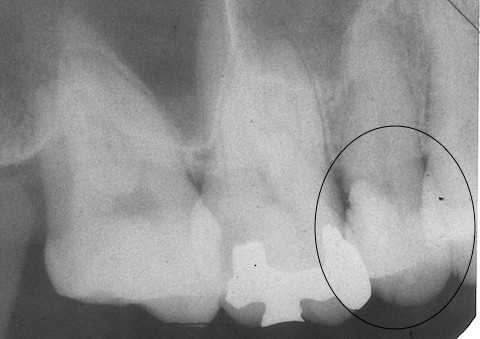

今日の充填治療55(遠心隣接面カリエス) 2023.12.21